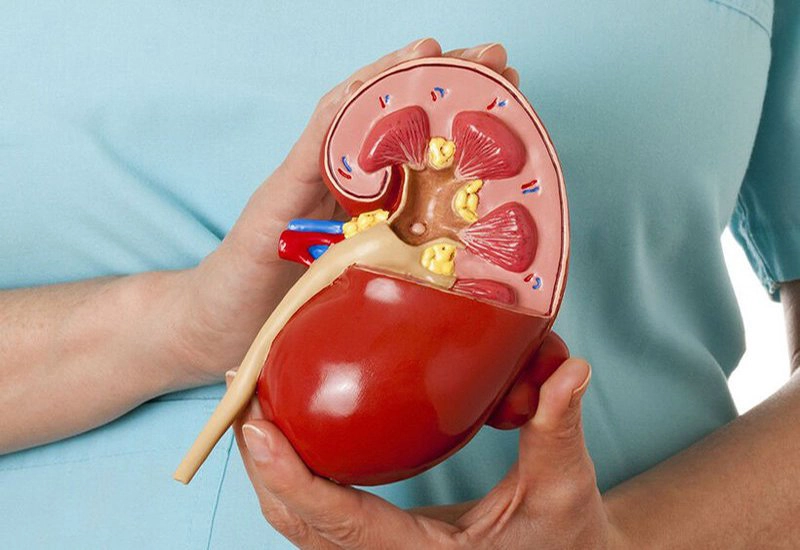

3. Thận: Bắt đầu lão hóa sau 40 tuổi

Sau 40 tuổi, chức năng thận ngày càng xuống dốc. Nếu mắc một số bệnh lý tiềm ẩn hoặc tuân thủ lối sống không khoa học thì sự suy giảm chức năng thận sẽ nhanh hơn.

– Dấu hiệu lão hóa: Huyết áp tăng, tiểu đêm nhiều lần, dễ mệt mỏi.

– Làm thế nào để làm chậm tốc độ lão hóa:

Không thể thiếu các bài tập thể dục chẳng hạn như đi bộ, chạy bộ, thể dục nhịp điệu.

Thận trọng khi dùng lâu dài các loại thuốc chống viêm không steroid, như thuốc giảm đau, thuốc cảm, thuốc hạ sốt. Cần uống thuốc theo lời khuyên của bác sĩ.

Cần kiểm soát huyết áp vì huyết áp cao không chỉ có thể gây ra bệnh thận mà còn đẩy nhanh sự tiến triển của tổn thương thận.

Cuối cùng, không ăn quá mặn: Nếu ăn quá mặn, cơ thể sẽ phải đào thải lượng muối dư thừa ra ngoài, làm tăng gánh nặng cho thận, đồng thời ăn quá mặn dễ dẫn đến cao huyết áp.